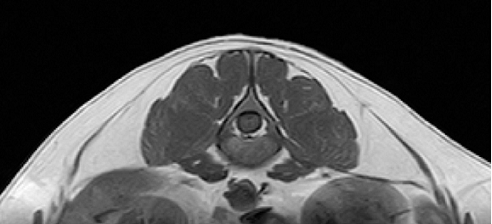

▲犬のほぼ正常な椎間板のMRI像(キャミックに依頼)